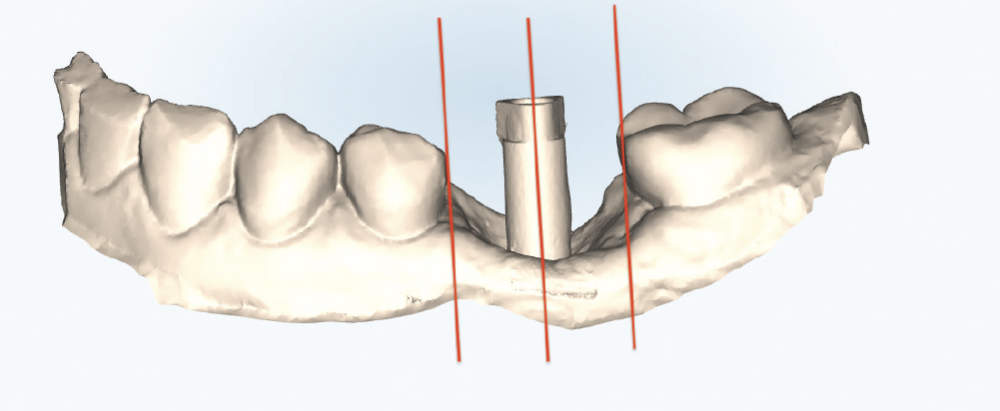

Thoroughly Scan the Scan Body Geometry

Thoroughly Scan the Scan Body Geometry. Complete, high-resolution capture of the scan body is non-negotiable. This is how laboratory software determines the precise three-dimensional position and angulation of the implant. The software matches the scanned scan body with its library file to establish the implant location in space. Scan from multiple angles to ensure all identifying features and surfaces are captured, as incomplete scan body data leads to misaligned restorations regardless of how perfect the rest of the scan appears. Verify that all reference markers, grooves, or geometric features are clearly visible in the acquired scan.

Implant post scan on left side of mouth

Implant post scan pointing down

Implant post scan close up

Verify the Scans Before Dismissing the Patient. Review all critical areas while the patient is still in the chair, ensuring complete scan body capture, accurate contacts, adequate tissue detail, and proper bite registration. Zoom in on critical areas to verify resolution and completeness. It takes only two minutes to verify a scan, but potentially days before a patient is able to return to your practice. Use the scanner’s analysis tools to identify distortions or artifacts.